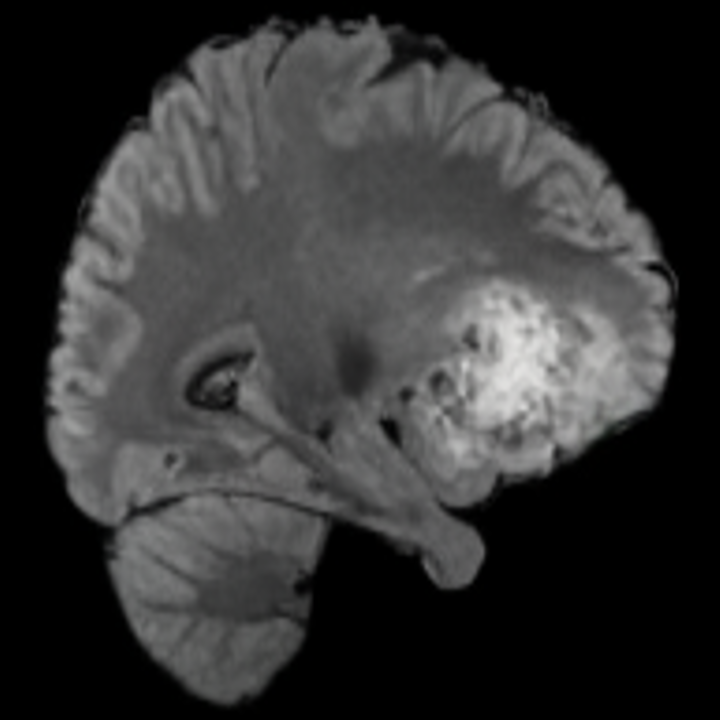

6.3 When does X-Diffusion Fail?

To see when and how X-Diffusion fails, we conducted an experiment on healthy brains (no tumour) using IXI dataset, by running an X-diffusion trained on BRATS brain tumor dataset. Our X-Diffusion achieved a PSNR of 35.86 dB on the IXI dataset despite being trained on the BRATS dataset. We then ran the tumour segmenter on the set of 582 healthy scans and corresponding generated MRIs. The segmenter predicted tumours in 9.9% of the real healthy brains and in 11.3% of the generated brain MRIs. Some of these tumor hallucination examples fron X-Diffusion generation are shown in Figure 10.